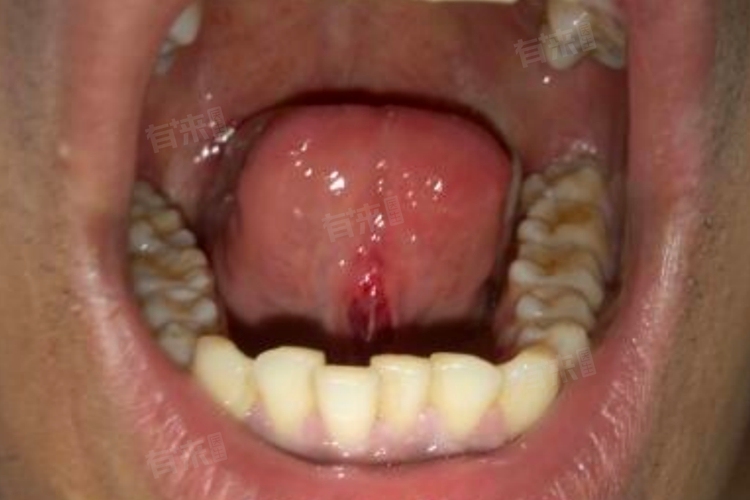

4、病毒感染:感染人乳头瘤病毒,可能引发舌下尖锐湿疣,表现为单个或多个小肉芽,表面粗糙呈菜花样。确诊后需及时就医,遵医嘱进行物理治疗,如冷冻、激光去除疣体,并配合药物治疗,降低复发风险。

5、肿瘤性病变:舌下的小肉芽也可能是良性肿瘤如乳头状瘤,或恶性肿瘤的早期表现。良性肿瘤生长缓慢,边界清晰;恶性肿瘤则生长迅速,伴有溃疡、出血等症状。一旦怀疑肿瘤,需尽快就医,通过病理检查明确性质,根据诊断结果选择手术切除或其他相应治疗方案。